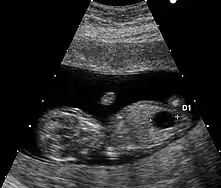

Échographie

Cette technique d'évaluation de la trisomie 21 (et des autres aneuploïdies) doit beaucoup au Professeur Kýpros Nicolaïdis de la Fetal Medicine Foundation de Londres.

Le marqueur échographique utilisé est la clarté nucale. La technique de mesure doit répondre à des critères stricts.

Il existe un autre marqueur échographique mais de mesure plus délicate : l'os propre du nez.

Aucun signe échographique n'est symptomatique de la trisomie 21. Néanmoins, un certain nombre d'anomalies mineures ou majeures qui se rencontrent plus fréquemment dans cette maladie chromosomique peuvent être mis en évidence.

- Anomalies mineures

- hypoplasie ou absence des os propres du nez ;

- fémur court, inférieur au 5e centile pour l'âge ;

- épaisseur de nuque supérieure à 6 mm à 20 semaines ;

- écartement important entre les premier et deuxième orteils ;

- brièveté de la deuxième phalange du cinquième doigt (brachymésophalangie) ;

- langue protruse…

- Anomalies majeures

- des malformations cardiaques (canal atrio-ventriculaire et en particulier) (dans 40 % des cas) ;

- des sténoses digestives (dans 10 à 18 % des cas) (image en « double bulle » de sténose duodénale).